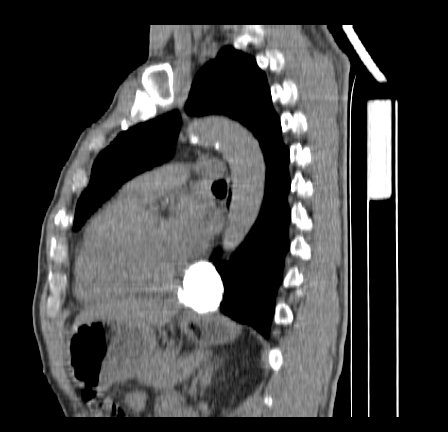

以下是引用影像孺子牛在2009-5-20 23:18:00的发言:[br]左侧后心膈角处类椭圆形钙化灶,最常见的是淋巴结钙化,但太大了不支持,其它如食管囊肿钙化、实性畸胆瘤等。何东西钙化真不好定。

以下是引用zbp537在2009-5-20 20:52:00的发言:[br]钙化灶,来源不好说。